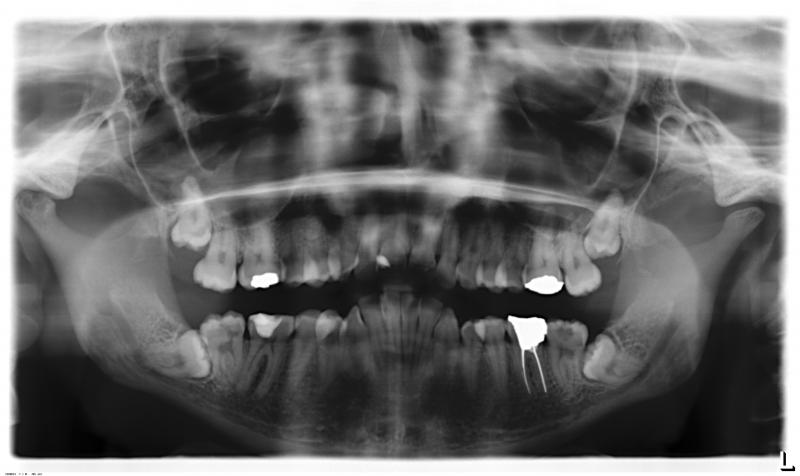

habe jetzt mein röntgenbild. vielleicht könnten sie mir eine art diagnose anbieten! oder so ähnlich!

[*]die Weisheitszähne entfernen lassen

[*]Karies sanieren (wenn vorhanden)

[*]Zahnspangen Therapie

[*]undichte Füllungen gegen hochwertige Füllungen mit der Zeit wechseln